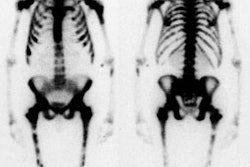

Pagets disease affects between 3% to 4% of the population over the age of 40 years and up to 10-11% after age 80 years [1]. Although the actual cause of Pagets disease is not known, a viral etiology has been postulated due to the presence of intra-nuclear inclusion bodies which resemble viral nucleocapsids within the osteoclasts of Pagetoid bones [1]. The most commonly involved bones are the vertebral bodies (30-75%), skull (25-65%), pelvis (30-75%), and proximal long bones (25-30%) [1]. Monostotic disease occurs in 10-35% of cases and is more often seen in the axial skeleton [1]. Polyostotic disease (65-90%) occurs more commonly [1]. Symptoms include pain, bowing deformities, kyphosis of the spine, and bone enlargement [1]. About 20% of affected patients are initially asymptomatic [1].

There are generally considered to be 3 phases to the disorder- lytic phase, mixed phase, and blastic phase. Initially, intense osteoclastic activity produces the lytic or incipient active phase. Lytic findings are more commonly seen in the skull and long bones. In the skull, involvement is refered to as osteoporosis circumscripta which produces well defined areas of lucency in the occipital and frontal bones [1]. The is notable absence of peripheral sclerosis surrounding the lucent areas [1]. Both the inner and outer calvarial tables are involved [1]. In the long bones, the process begins in the subchondral area of the epiphysis and extends along the shaft in a characteristic wedge-shaped ("flame" or "blade of grass") appearance. The lytic phase is followed by the mixed or fibrous phase in which bone marrow is replaced by very vascular fibrous tissue. There is coarsened thickening of the trabecular pattern and cortex [1]. In the vertebral bodies, osteoblastic activity is seen along all 4 margins producing a "picture frame" appearance [1]. There is also "squaring" of the normal concavity of the anterior margin of the vertebral body [1]. Disorganized ossification and deformities or fractures may occur. Finally, the disorder become quiescent with the involved bone generally appearing enlarged and sclerotic.

During the lytic portion of the disease lesions may demonstrate uniform increased tracer accumulation, or may have relative photopenia in their center producing a "donut" appearance. In the long bones, increased tracer activity is particularly prominent along the advancing edge of the disorder. Scintigraphy is more sensitive than plain films for disease detection and extent during the lytic phase.

During the fibrous phase, the bone scan demonstrates marked

increased uptake of tracer

in the involved areas. The bone scan can be used to document the

effectiveness of therapy

in these patients. Later, during the sclerotic phase, the bone

scans will begin to show

less intense tracer accumulation and may become normal.

Pagets Disease: Multiple sites of involvement by Pagets disease including the jaw. |